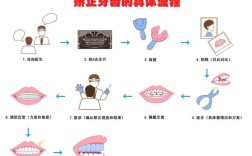

矫正阶段:

- 隐形矫正通常分为几个阶段:

- 排齐与整平阶段: 将牙齿排齐,建立基本弓形。

- 关闭拔牙间隙/集中收缝阶段: 如果拔了牙,需要关闭间隙;或者集中关闭牙缝。

- 咬合精细调整阶段: 调整牙齿的咬合关系,确保上下牙齿能完美咬合。

- 保持阶段: 矫正结束后,需要佩戴保持器以防止复发(这通常不计入矫正时间,但至关重要)。

- 每个阶段的时间不同,特别是关闭间隙和精细调整阶段往往耗时较长。

- 咨询专业正畸医生是关键: 只有经过全面的口腔检查(包括拍X光片、取牙模、拍照等),由正畸医生进行专业评估和方案设计后,才能得到一个相对准确的预估时间。